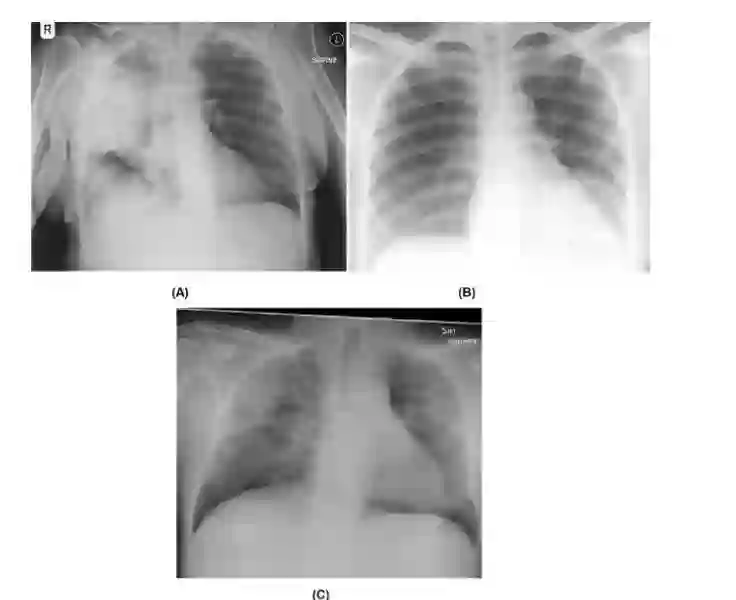

图1: 样本COVIDx数据集上的前后胸片图像:(a)细菌感染、(b)非COVID-19病毒感染和(c)COVID-19病毒感染。